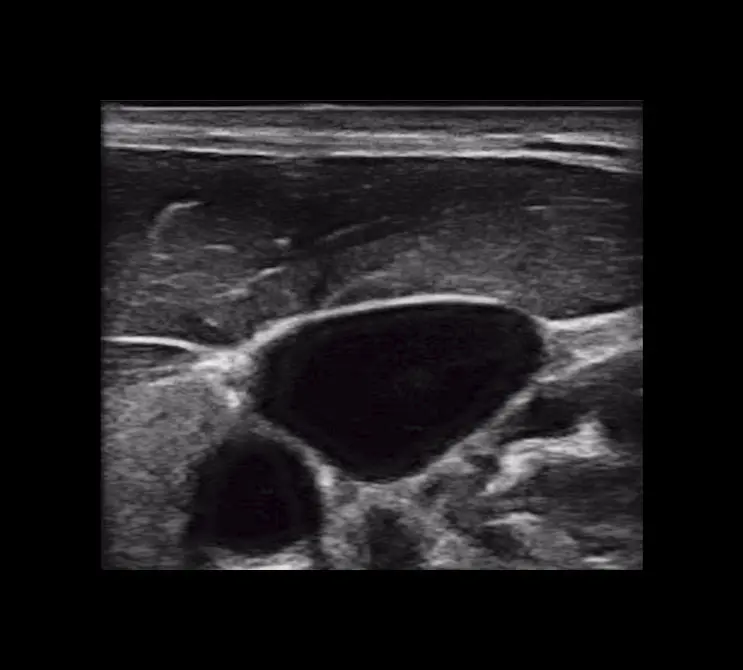

T-Mode es un enfoque innovador para la educación en ecografía diseñado para mejorar sus habilidades de escaneo utilizando la potencia de la inteligencia artificial en aplicaciones de Estética y Cirugía Plástica. Cette technologie novatrice superpose des couleurs distinctes, des motifs et des étiquettes pour identifier et différencier les structures anatomiques et les couches de tissu.